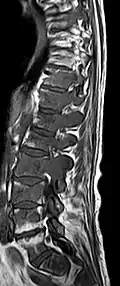

- Vergleich CT / MRT bei osteolytischen Metastasen eines Mammakarzinoms in der Wirbelsäule

-

Sagittal rekonstruierte CT, Darstellung im Knochenfenster. Da die Patientin multiple Metastasen in allen Körperregionen hatte, konnte sie die Arme nicht für die Untersuchung nach oben nehmen, weshalb die Hände mit abgebildet sind. -

Sagittal rekonstruierte CT, Weichteilfenster. Neben den Metastasen in der Wirbelsäule, die teilweise nach hinten in den Spinalkanal einwachsen, auch Metastasen im Brustbein. Zusätzlich Lebermetastasen. -

Sagittale native T1-gewichtete MRT -

Sagittale native T1-gewichtete MRT. Deutlich sichtbar die Ausdehnung bis in die Bogenwurzeln.